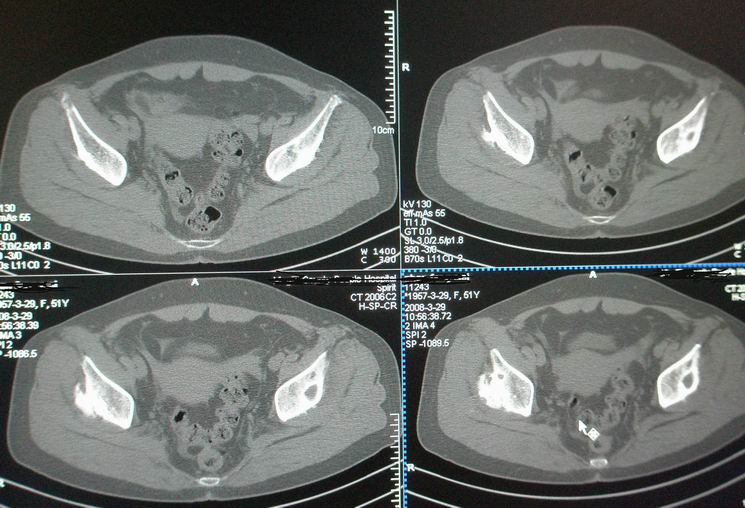

标题: CT12535:女,51岁.双髋痛多年,近加重,左腿难伸直. [打印本页]

标题: CT12535:女,51岁.双髋痛多年,近加重,左腿难伸直.

双髋无菌坏死(重度)??

先天性髋臼发育不良性骨病。双侧股骨头改变为继发性退变。

成人髋臼发育不良性骨关节病.是由于髋臼先天发育不良、髋臼角变大,部分股骨头位于髋臼以外,持重部位少,长期站立、负重造成髋臼退行性骨关节病,主要x线表现是:髋臼变浅平,髋臼角增大,ce角小于30度,髋关节骨性关节面增生硬化,关节间隙变窄,髋臼及股骨头可有囊变.但股骨头变形轻微,与股骨头坏死相比,预后好,可两三年变化不大,而股骨头坏死早期关节间隙不窄或增宽,等到间隙变窄时股骨头已明显变形.

鉴别:股骨头缺血坏死

双侧髋关节退行性骨关节病

(双侧股骨头变形明显,但坏死、囊变不明显)

双侧股骨头坏死!继发性退变。

既然双髋疼痛多年,不会是第一次检查吧,病人以前的诊断资料能否提供,病人的其他关节都正常吗?有没有东北地区居住史?首先考虑成人股骨头无菌坏死ⅴ期,其次要考虑大骨节病。

此病人从未看过病.家穷,临床医生要她做了椎间盘,未发现明显异常.我免费给她做了双髋.是南方人.十几年前痛过,自行贴膏药,开始自我感觉还好后来不行.近两年痛加重.下登困难.左腿不能伸直.